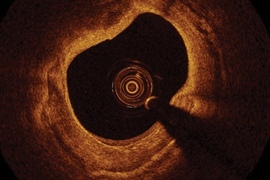

St Jude OCT system to aid treatment of coronary artery disease

Launched in Japan, the imaging technique provides physicians with a better view of narrowed coronary arteries.